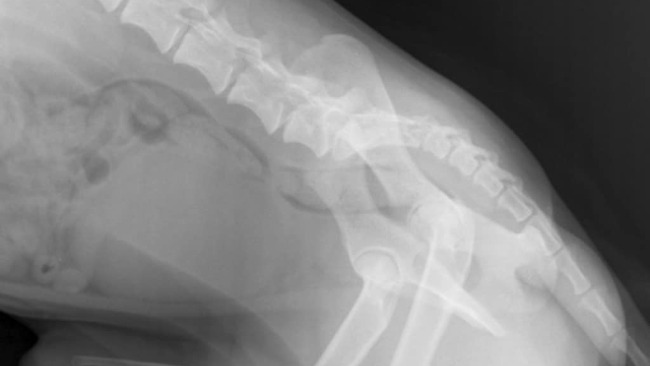

W samym środku lasu, z dala od ludzi i pomocy, znaleziono małego, biszkoptowego psiaka — wycieńczonego, zdezorientowanego, który ciągnął za sobą tylne łapy. Wszyscy, którzy go zobaczyli, byli przekonani, że to koniec… że ma przerwany rdzeń kręgowy i już nigdy nie stanie na nogi.

Na szczęście Gucio trafił na dobrych ludzi, którzy nie przeszli obok obojętnie.Został zgłoszony do pani Magdy, prowadzącej schronisko w Rytlowie, która natychmiast zorganizowała dla niego pomoc i opiekę.Po szybkiej konsultacji w przychodni weterynaryjnej Hesse we Włoszczowie, Gucio trafił do gabinetu Cztery Łapy w Kielcach, gdzie opiekę nad nim przejął dr Kabała.Tam rozpoczęła się walka o jego zdrowie i powrót do sprawności — badania, diagnostyka, operacja i rehabilitacja .